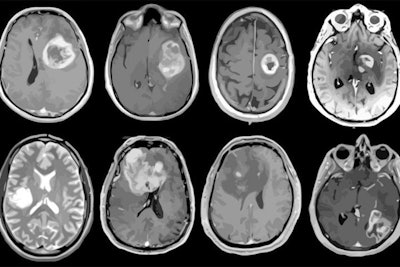

Using MRI, a team of more than 40 investigators has created a profile of the genes, proteins, infiltrating cells, and signaling pathways of the deadly brain cancer glioblastoma. The findings could translate to better patient care, according to the authors of a new study published February 11 in Cancer Cell.

In the current study, the authors used MRI to create a "map" of glioblastoma that included data from 99 tumors, measuring proteins in the samples as well as protein modifications called phosphorylation and acetylation, which influence how cells communicate.